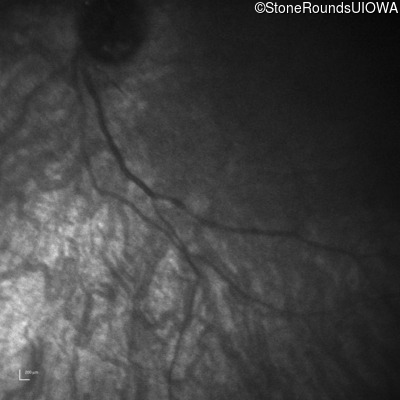

Infrared Fundus Photograph - Right -

No Light Perception

Infrared Fundus Photograph - Left -